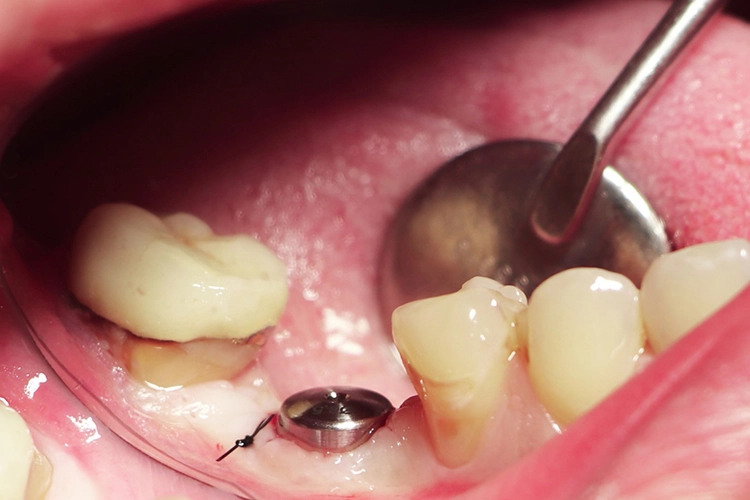

Im nächsten Schritt erfolgte die vollständig navigierte Implantation des Microcone-Implantates (Ø 5,0 mm, 9 mm Länge) in der Region 46 (Abb. 8-14) nach dem vom Hersteller empfohlenen Bohrprotokoll, das sich nach Knochenqualität und Implantatdurchmesser richtet. Die Chirurgie-Kassette (Abb. 6) ist übersichtlich aufgebaut und intuitiv zu bedienen. Zur schonenden Präparation des knöchernen Implantatbetts stehen je nach Implantatdurchmesser und Knochenqualität bis zu fünf verschiedene Bohrertypen mit Farbcodierung zur Verfügung. Das Implantat war für eine gedeckte Einheilung vorgesehen und der Kieferkamm wurde durch Nahtlegung speicheldicht verschlossen (Abb. 15).

Die Dokumentation des Implantatsitzes erfolgte mit einer postoperativen Panoramaschichtaufnahme (Abb. 16). Nach der gedeckten Einheilung erfolgte im Juni 2021 die geschlossene Implantatabformung mit Impregum. Abbildung 17 bis 25 zeigt den Ablauf von der Inzision drei Monate nach Implantation bis zum Einsetzen des Hybrid-Abutments mit Titan-Klebebasis und Zirkonaufbau bis zur finalen Zirkonkrone, die aufgrund einer Erkrankung der Patientin etwas später als vorgesehen im Juli 2021 eingegliedert werden konnte. Die Versorgung der insuffizienten Einzelkrone 47 erfolgt auf Patientenwunsch zu einem späteren Zeitpunkt.